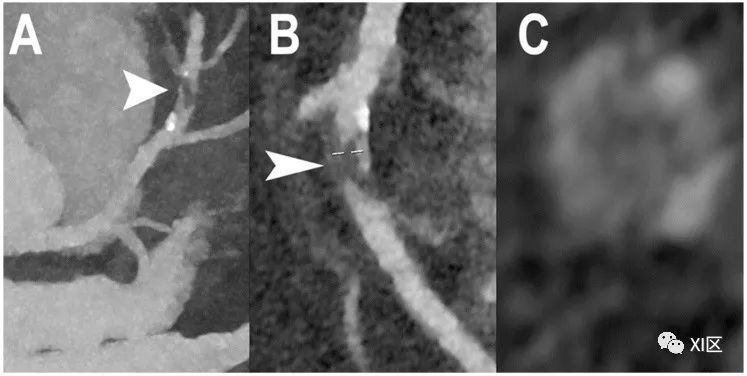

阻塞性CAD的心脏PCCT示例。图中显示的是左前降支(LAD)中段(A-C)严重狭窄的示例。斑块((A,B);箭头)主要呈非钙化表型,内核密度较低(C)。本例采用高分辨率模式重建(空间分辨率为100 μm,层厚为0.2 mm)。